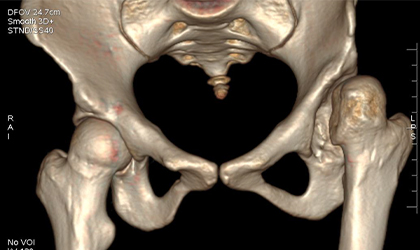

26-year-old woman diagnosed with hip dysplasia characterized by a shallow hip socket. She underwent a left total hip replacement using a specialized prosthesis known as the S-ROM system. Additionally, bone grafting was performed to reconstruct and reinforce the socket walls for better implant support.This is one of the youngest girls I have done a hip replacement in. Did her right hip when she was 13 and the left a year later. She is a blood cancer survivor. She had collapse of both her hips related to chemotherapy (which actually saved her life). She had ceramic bearings. Presently totally symptom free pursuing her higher studies.

Detailed imaging and clinical evaluations revealed developmental dysplasia of the hip. A comprehensive surgical plan was developed, considering the unique anatomy.